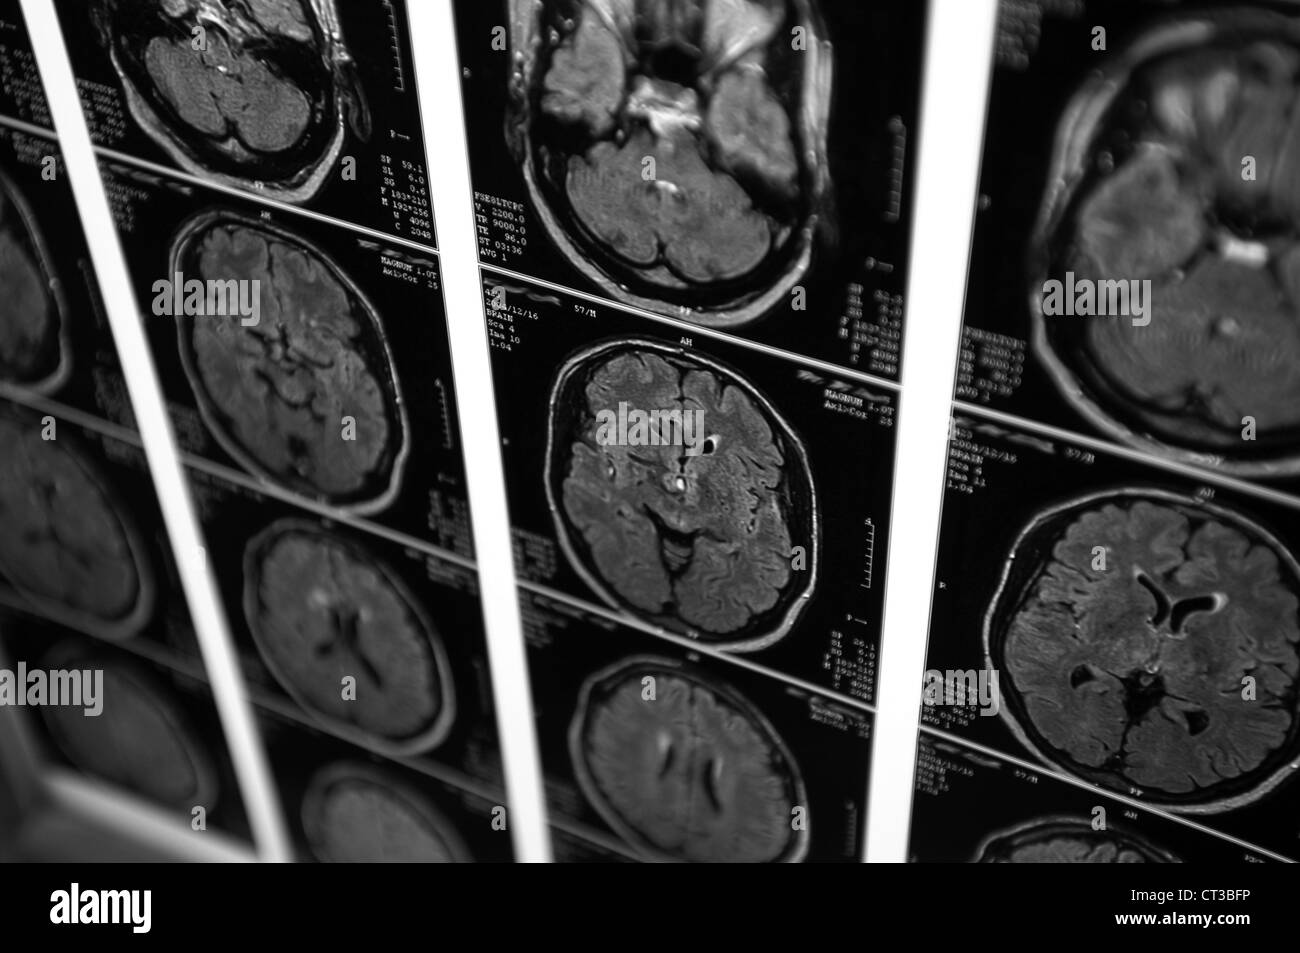

Une série de scanner (CT) d'un jeune homme. Banque D'Imageshttps://www.alamyimages.fr/image-license-details/?v=1https://www.alamyimages.fr/photo-image-une-serie-de-scanner-ct-d-un-jeune-homme-49247402.html

Une série de scanner (CT) d'un jeune homme. Banque D'Imageshttps://www.alamyimages.fr/image-license-details/?v=1https://www.alamyimages.fr/photo-image-une-serie-de-scanner-ct-d-un-jeune-homme-49247402.htmlRMCT3BFP–Une série de scanner (CT) d'un jeune homme.

Une série de scanner (CT) d'un jeune homme. Banque D'Imageshttps://www.alamyimages.fr/image-license-details/?v=1https://www.alamyimages.fr/photo-image-une-serie-de-scanner-ct-d-un-jeune-homme-49247398.html

Une série de scanner (CT) d'un jeune homme. Banque D'Imageshttps://www.alamyimages.fr/image-license-details/?v=1https://www.alamyimages.fr/photo-image-une-serie-de-scanner-ct-d-un-jeune-homme-49247398.htmlRMCT3BFJ–Une série de scanner (CT) d'un jeune homme.